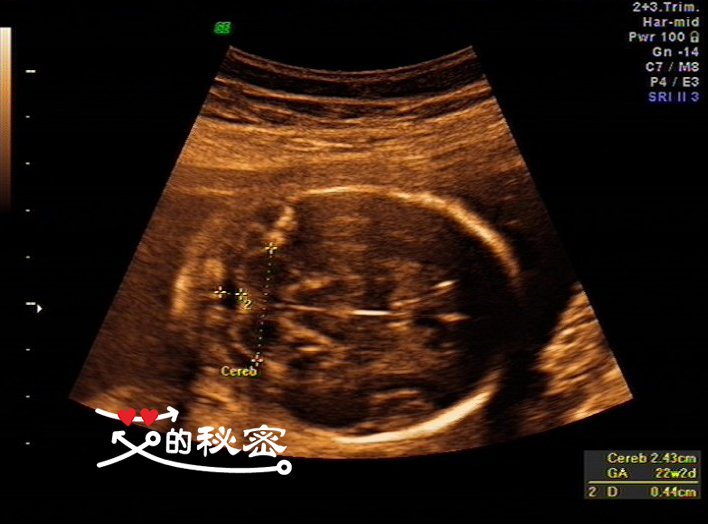

5、胎儿头部:颅骨环未见明显缺损,大脑回声可见,脑中线居中,两侧丘脑可见,侧脑室未见增宽,小脑形态未见异常,小脑蚓部可见,后颅窝未见增大。英文的意思:CEREB小脑横径。